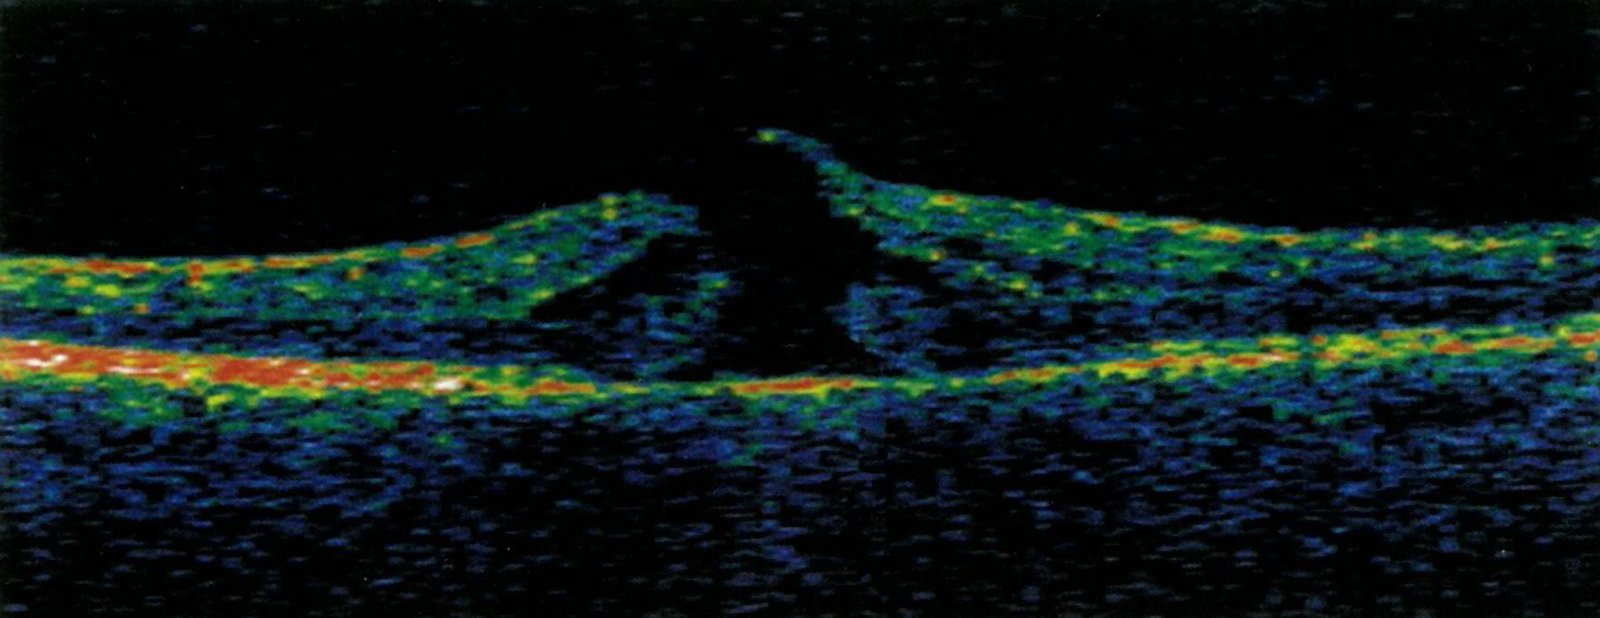

Macular hole

• Definition:central small break in the macula

• Etiology

• Idiopathic

• Secondary (e.g., to vitreous detachment, due to trauma, following laser therapy)

• Clinical features (stage-related)

• Metamorphopsia

• Central visual field losses

• Severe reduction of visual acuity

• Treatment: vitrectomy with removal of epiretinal membranes and the internal limiting membrane of the retina